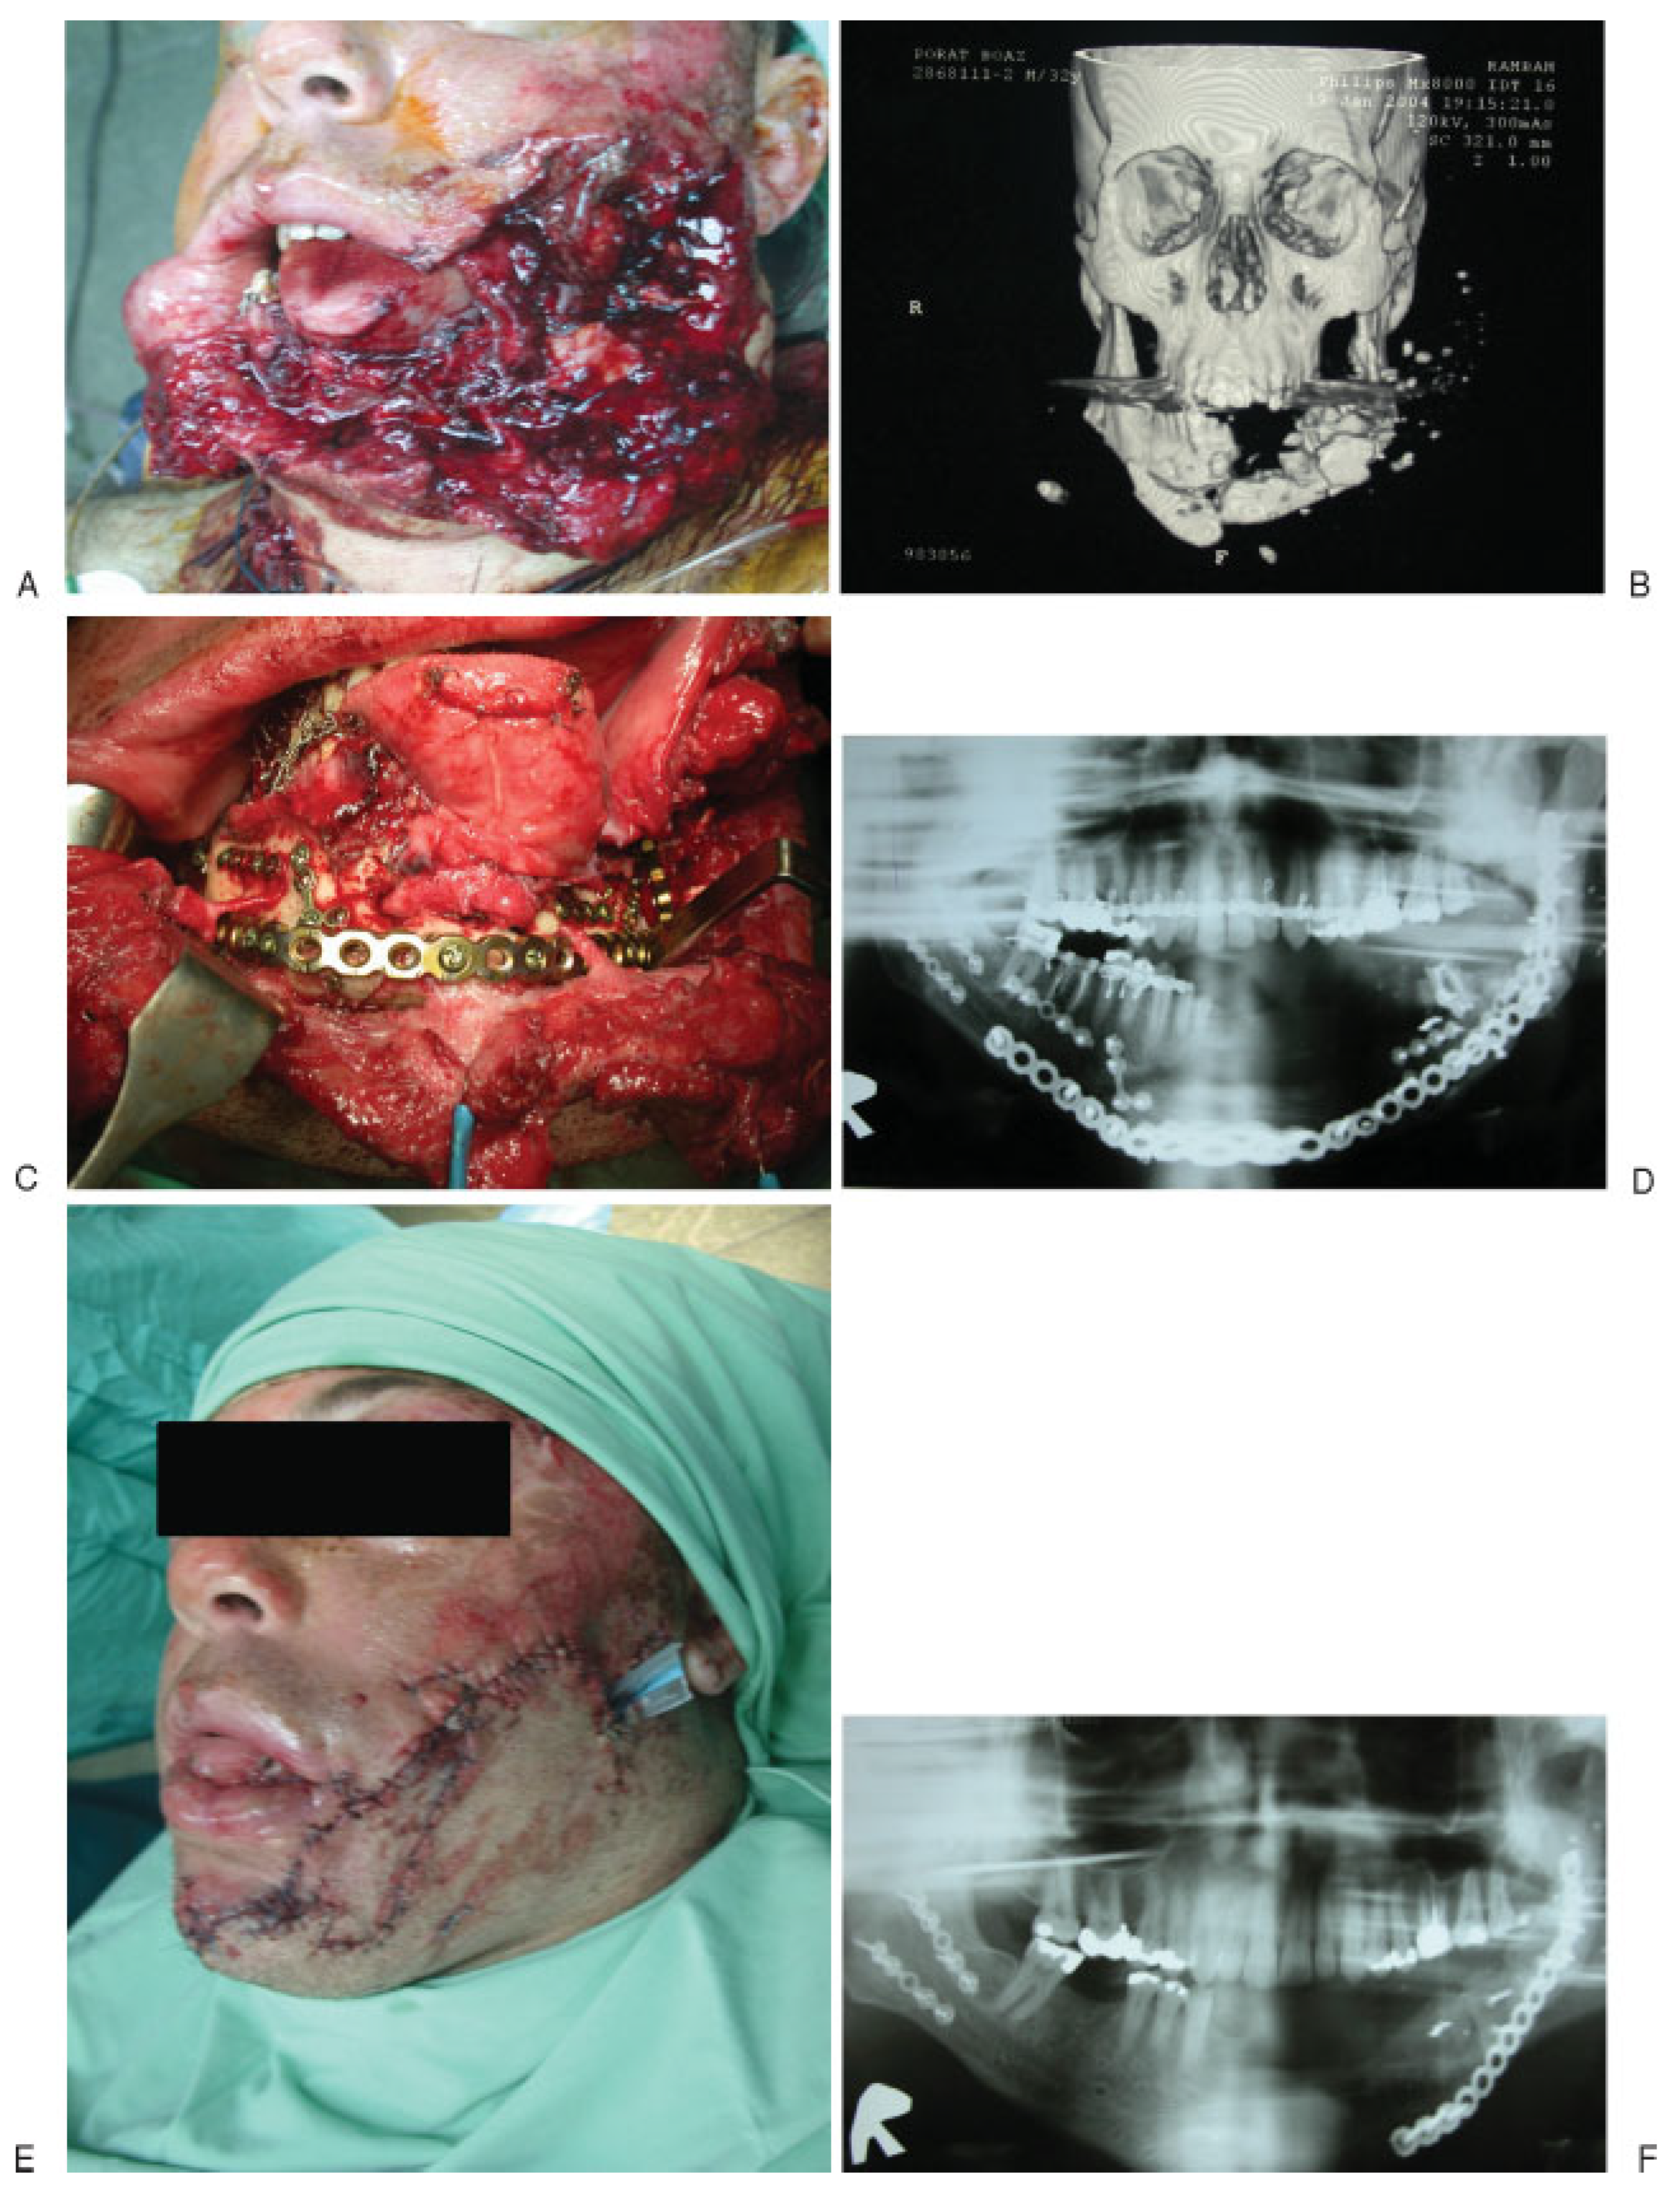

- Primary lifesaving and organ preservation procedures: intubation upon arrival, cervical spine radiography, direct pressure and packing for hemostasis, and hemodynamic stabilization in accordance with ATLS protocols.

- Imaging: multiplanar computed tomography (CT), 3-D CT, CT angiography in all maxillofacial ballistic injury patients, and superselective angiography in midface injuries.

- Restoration and stabilization of occlusal relations via maxillomandibular fixation. Facial bony framework stabilization and rigid fixation using load-bearing bicortical plates (2.4 mm) in the mandible and monocortical plates (2.0 mm) in the remaining facial skeleton.

- Tissue preservation: meticulous primary closure of the intraoral and extraoral soft tissue to provide full coverage of the comminuted fractures.

- Immediate bone grafting of the midface, nasal orbital, and zygomatic structures using calvarial free bone grafts, if no major head trauma is present to contraindicate calvarial bone grafting, if so anterior iliac crest bone grafting is harvested.

- Secondary reconstruction of avulsive mandibular injuries using iliac crest bone grafts during the first weeks following trauma. Implementation of vascularized free grafts only in cases of massive tissue avulsion or in cases of primary reconstruction failures.